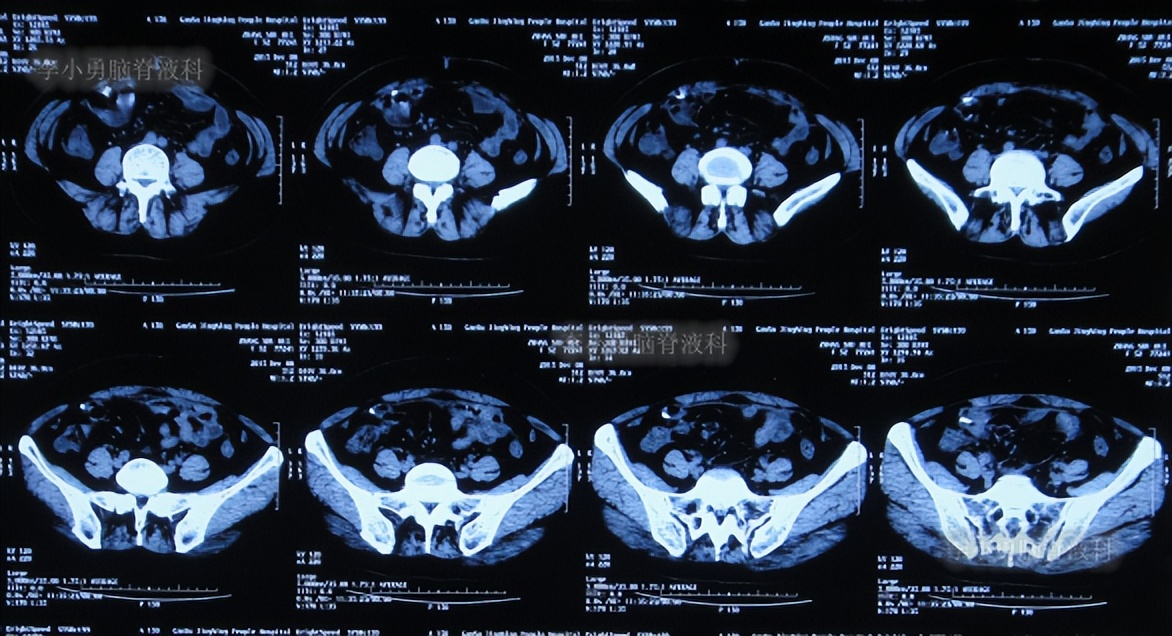

出院后1年零4个月即2015年12月8日(脑室腹腔分流术后1年零5个月),又因“肠梗阻(不全性)”,第2次住入之前手术的医院,当天查腹部CT:仍然有积液( 图-6 )。给予静脉抗感染、灌肠通便等对症支持,治疗2周后,肠梗阻症状改善后出院。

图-6: 2015年12月8日腹部CT

住院次日即2016年8月17日,查腹部CT:仍有腹腔积液( 图-8 )。

图-8: 2016年8月17日腹部CT